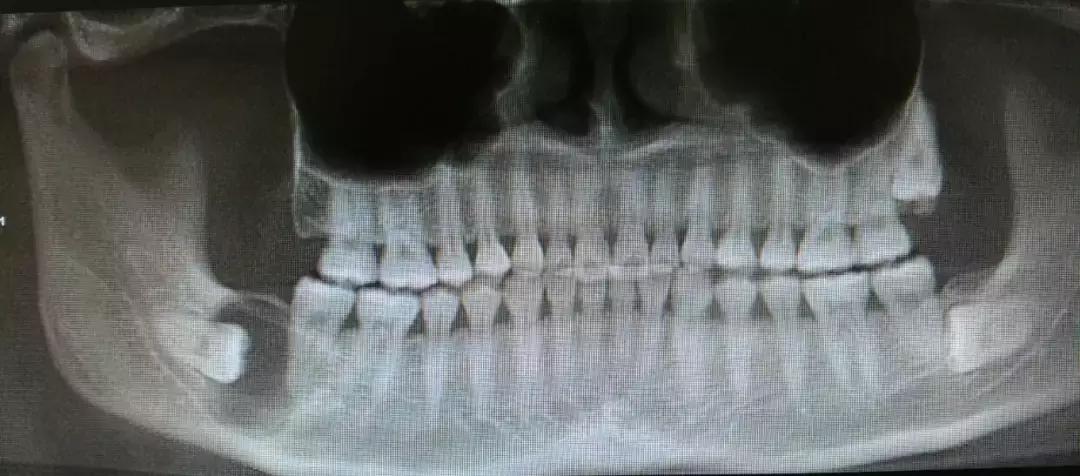

阻生智齿和神经的关系↓

对待这种「骑」在神经上的智齿要以医生建议为主,即使拔也一定要选择微创拔哦。这个危险距离,一锤子下去,神经可就很难保住了。